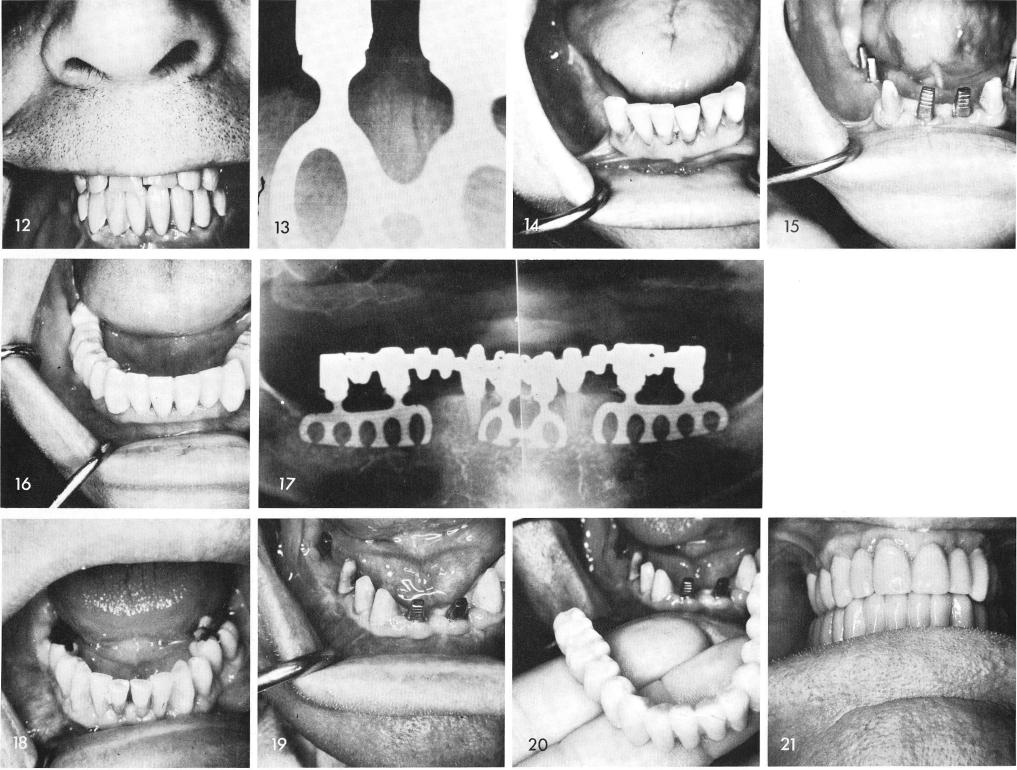

Midline blades are most often used in the form of a "socket blade" in between two cuspids immediately after the four periodontally involved incisor teeth are removed. Posteriorly, blades are also inserted in the edentulous areas, figs. 14, 15. A final acrylic over gold full arch fixed prosthesis was the material of choice, fig. 16. A final x-ray, fig. 17.

Similarly, a socket blade is inserted between both cuspids after the incisor teeth are re-moved and only one posterior blade is needed in the right posterior edentulous area, figs. 18, 19. The porcelain bridge is cemented as soon as possible, figs. 20, 21. An x-ray shows the completed case, fig. 22.